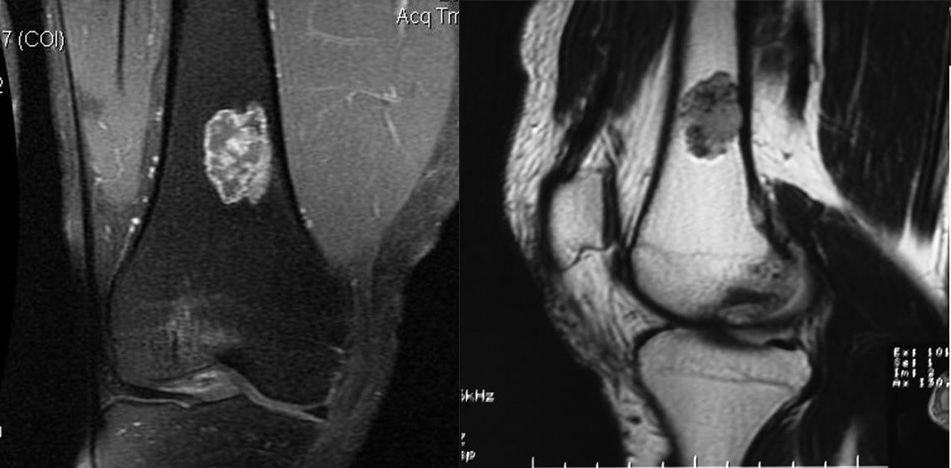

②非骨化性纤维瘤:多发生于长骨骨皮质内或骨皮质下,为多囊状、分叶状软组织密度,周围可见较厚硬化环。

注:9 岁女孩,左侧胫骨近端干骺端 NOF。胫骨近端干骺端徧心性溶骨性病变, 以后缘皮质为基底突向髓腔,浅分叶状,边缘清晰锐利硬化。